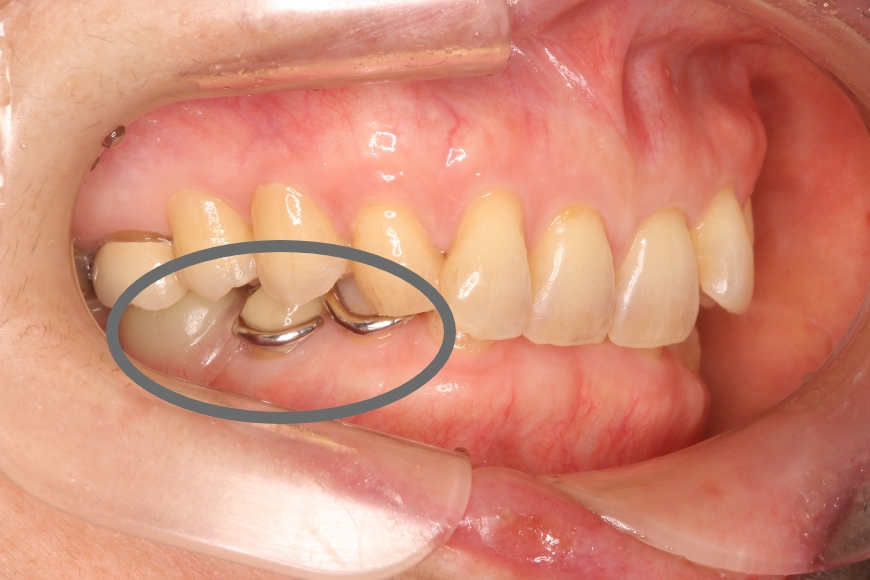

20代女性 上の奥歯へのジルコニア治療およびメタルタトゥーの除去

治療前①

治療後①

治療前②

治療後②

治療内容 奥歯の被せものをやり直したい、また、歯ぐきが黒くて気になるとのことで来院されました。

金属の被せの表面にプラスチックが張り付けてあり、また、使用している金属が溶け出し、歯ぐきが黒くなっていました(メタルタトゥー)。

装着してある全ての金属を除去後、歯ぐきのメタルタトゥーにレーザー照射を行い、健康なピンク色の歯ぐきを回復しました。その後、審美的および耐久性に優れるジルコニアの被せものを装着しました。

治療後は金属アレルギーのリスクがゼロとなり、メタルタトゥーが起こる心配もありません。

治療期間・回数 治療期間:約3ヶ月程度

通院回数:5回程度

治療費用(総額)

132,000

( ジルコニア 110,000円、メタルタトゥー除去1か所 22,000円。時期や手法により異なる場合があります。)

副作用・リスク ・ジルコニアは、保険治療のプラスチックに比べ硬く耐久性がありますが、強い力が加わるとごくまれに割れたり欠けたりすることがあります。

・メタルタトゥー除去後は、一時的な出血・腫脹・疼痛が生じる場合がまれにあります。

・喫煙や他の色素沈着因子により、再発の可能性があります。